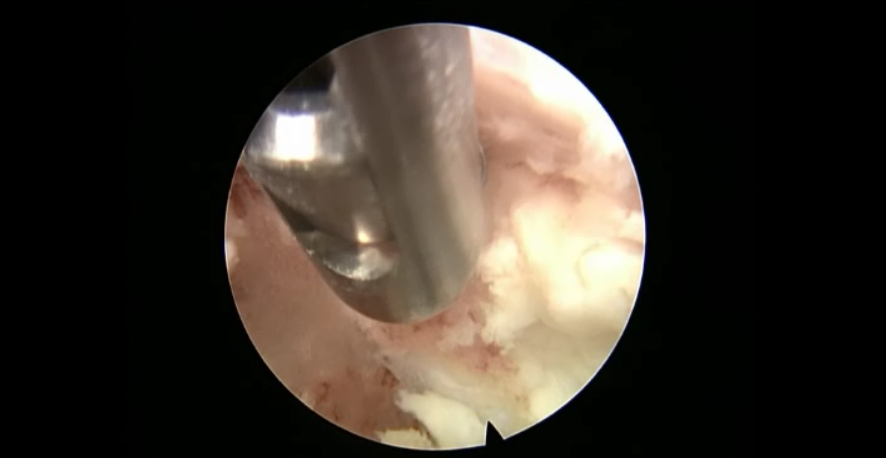

点击以上图片,查看术中视频(超链接:http://res.orthonline.com.cn/video/case5---30.mp4)